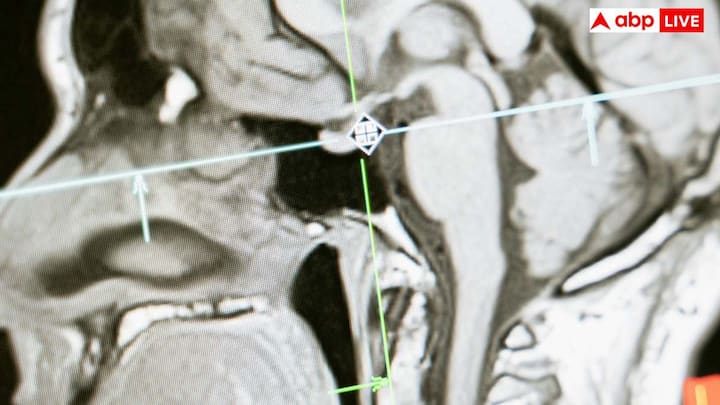

हम लोग अक्सर यही सोचते हैं कि डिहाइड्रेशन से शरीर में बस थोड़ी पानी की कमी होती है और इसका कोई खास असर नहीं पड़ेगा, लेकिन यह सोच बिल्कुल गलत है. शरीर में पानी की कमी यानी डिहाइड्रेशन से शरीर को कई तरह की गंभीर दिक्कतों का सामना करना पड़ सकता है. अगर शरीर डिहाइड्रेशन का शिकार हो जाता है, तो इसका सबसे गहरा असर हमारे मस्तिष्क यानी दिमाग पर पड़ता है. डिहाइड्रेशन की स्थिति में दिमाग सिकुड़ सकता है, क्योंकि शरीर दिमाग में मौजूद पानी को खींचना शुरू कर देता है. इससे दिमाग के टिश्यू यानी ऊतक सिकुड़ने लगते हैं.

जब हम पर्याप्त मात्रा में पानी नहीं पीते और शरीर में डिहाइड्रेशन बढ़ जाता है, तो खून में नमक और अन्य तत्वों की मात्रा बढ़ जाती है. इससे खून गाढ़ा हो जाता है. खून को पतला करने के लिए शरीर दिमाग की कोशिकाओं से पानी खींचना शुरू कर देता है. जैसे ही कोशिकाओं से पानी निकलता है, दिमाग का आकार सिकुड़ने लगता है.

वैज्ञानिक शोध बताते हैं कि जब शरीर में पानी की कमी होती है, तो किसी भी काम को करने के लिए दिमाग को ज्यादा मेहनत करनी पड़ती है. यह स्थिति लंबे समय तक बनी रहे, तो यह दिमाग के लिए नुकसानदायक साबित हो सकती है.